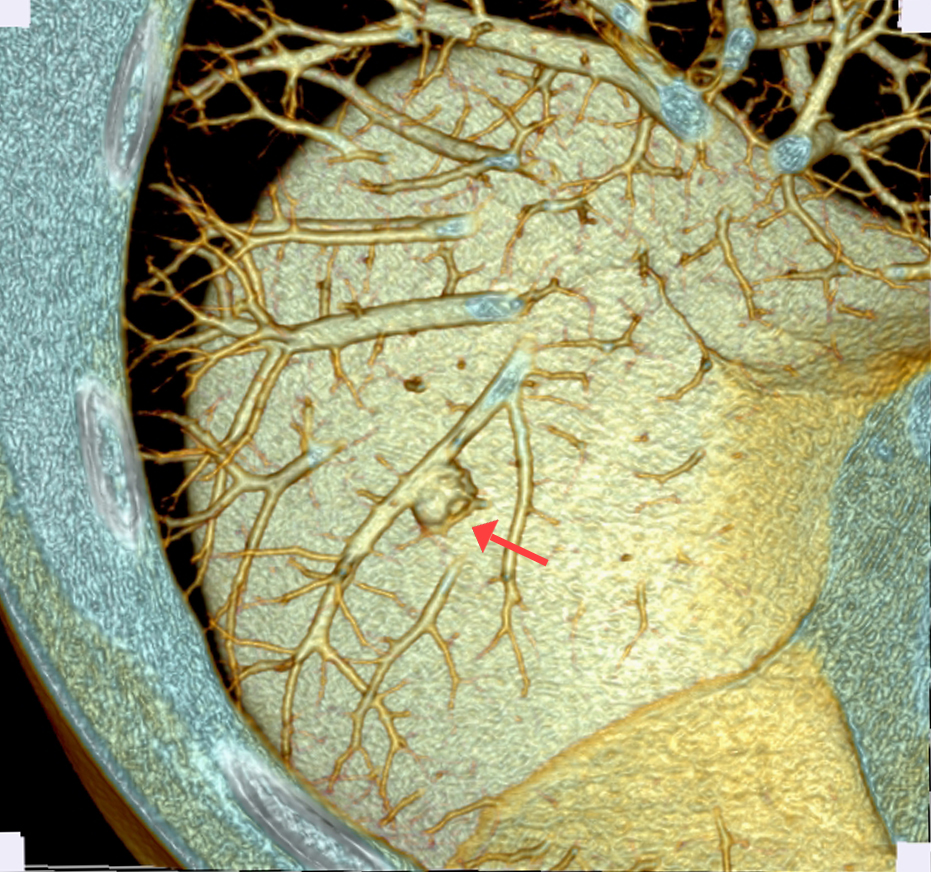

利用小FOV,在相同矩陣狀態(tài)下,視野內(nèi)像素減小,可以獲取高分辨率的優(yōu)質(zhì)圖像, 增強(qiáng)了組織間的密度分辨率和空間分辨率,同時(shí)可以根據(jù)原始的數(shù)據(jù)來進(jìn)行后續(xù)重建處理,如:MPR、VR等,可以充分展現(xiàn)出胸膜牽拉征、分葉征、空泡征、毛刺征、支氣管血管集束征等肺癌相關(guān)性特征,這是常規(guī)掃描無法比擬的。

中心病例:林先生,吸煙史20年左右。影像診斷:右肺下葉實(shí)性結(jié)節(jié),考慮腫瘤性病變可能性大,術(shù)后證實(shí)是肺腺癌。